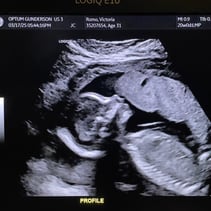

Greetings! I’ve been away from my updates for a couple of weeks, so lets get you caught up on all the things! First off, we had our Anatomy Scan today and hit the half way mark of the pregnancy. WOW. Our baby girl is doing so so well. From head to toe, she’s about 9-10inches and weighs 12oz. A week or two ago I stopped having all pregnancy symptoms besides the obvious physical changes. This was awesome but also made me a little uneasy. I also have not felt much movement and waiting 4 weeks for my 20 week appointment was starting to make me very antsy in a horribly, anxious way. Having a miscarriage the first time around has really made it difficult to relax and feel confident that everything is going well. Last week Steven went ahead and bought me a Doppler to listen to our baby’s heart beat at home while we waited for our next appointment. Once it came in and I found that wonderful sound of her heart, whew! Instant relief. Today was even better! Not only is SHE healthy, but so am I! I started going to the gym a few days out of the week and signed myself up for a 4 week Prenatal Yoga class that takes place every Saturday. My blood pressure today was 118/72 and weighing 129 which is 4 pounds more than my last appointment. I feel wonderful and even more excited than I was before to meet our girl! We’ve started clearing out the room that will be her nursery and are so grateful to the friends and family that have already started pouring their love into us and our baby with the registry gifts! Steven also surprised me with setting me up to visit family in Texas next month during my Spring Break from work. What a guy. 💕 I hope you all enjoy these photos! You‘ll see her profile with her cute little nose! There’s one of her foot, one of her crunched up with her legs bent, a crazy one of her that looks like a Halloween photo, and it’s hard to tell but one of her lips and nose. She was spinning and drinking and kissing us while she was having her first photoshoot. I will start feeling her more in the next couple of months. I have an anterior placenta so it makes things a little harder to feel since its placed in the front of my uterus. She is having fun, nonetheless. That’s all for now! We love you aaalllllll. A note from Steven: we could clearly tell during the sonogram that she gets her dance moves from her daddy.